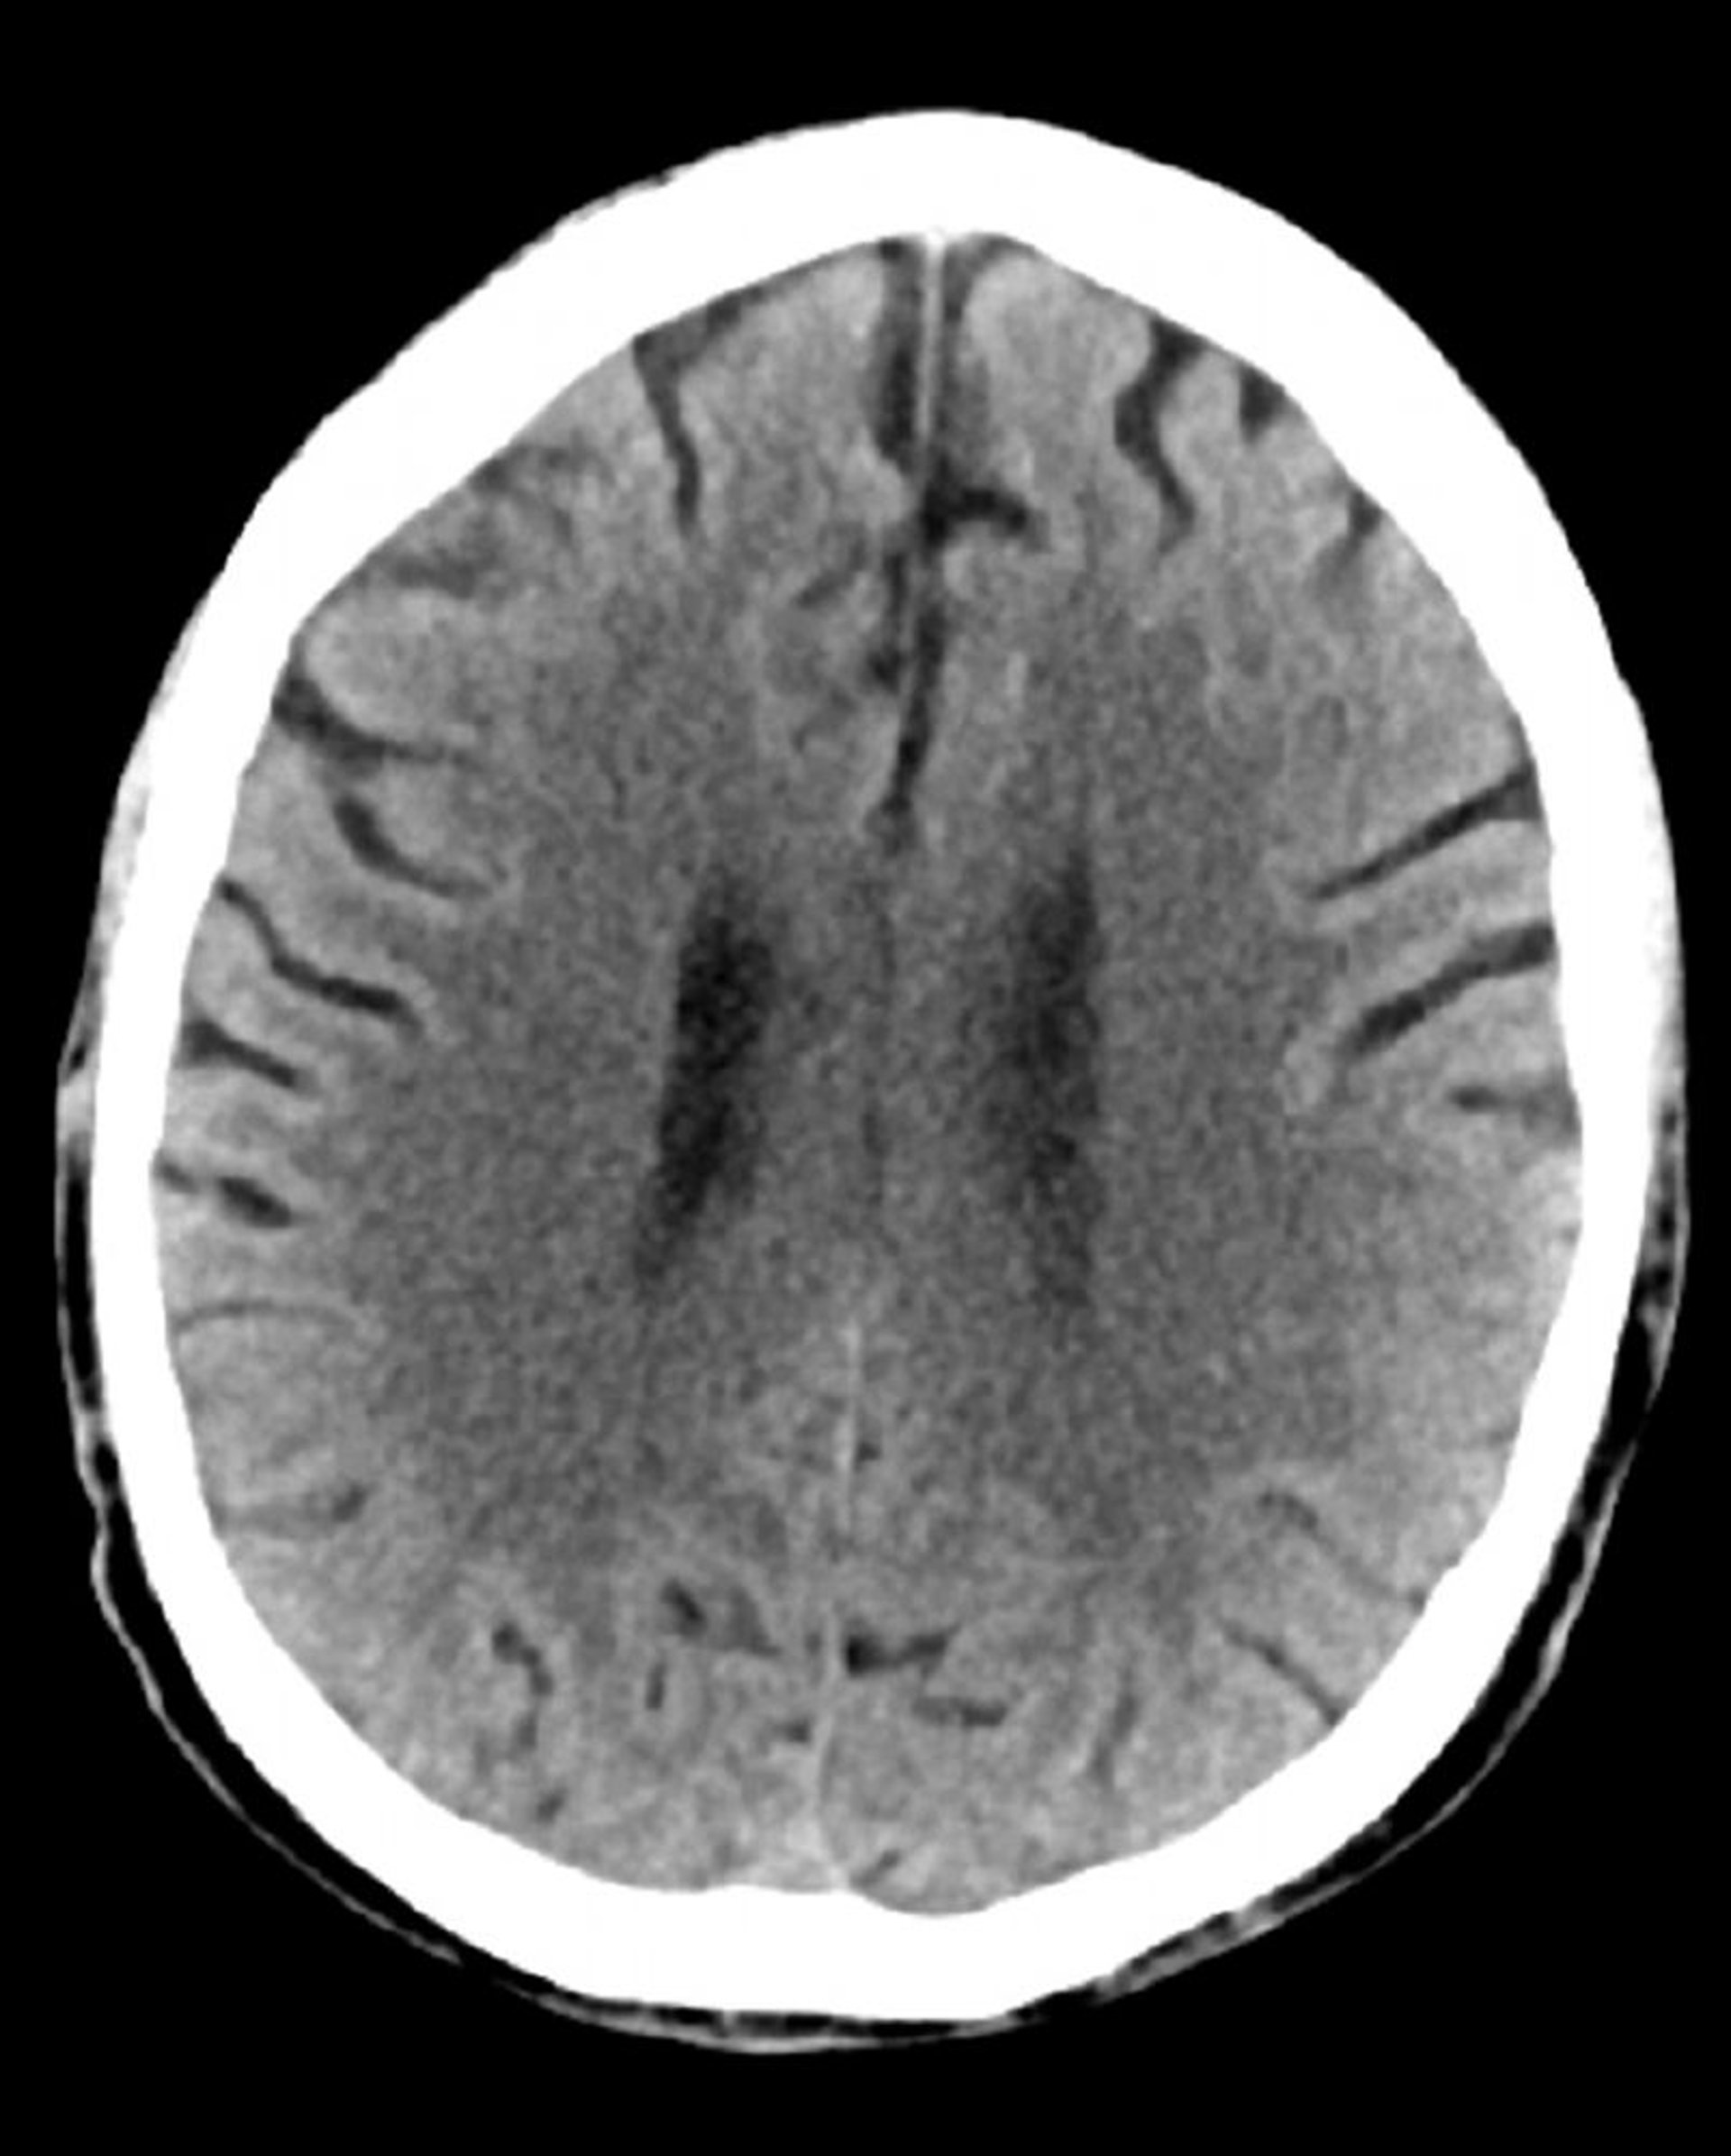

TC cerebrale normale (adulto di 74 anni), slide 3

Questa immagine è una normale TC della testa di un adulto di 74 anni. Rispetto alla normale TC della testa di un soggetto di 30 anni, i ventricoli e i solchi sono più grandi. Questi reperti sono normali in questa fascia d'età.